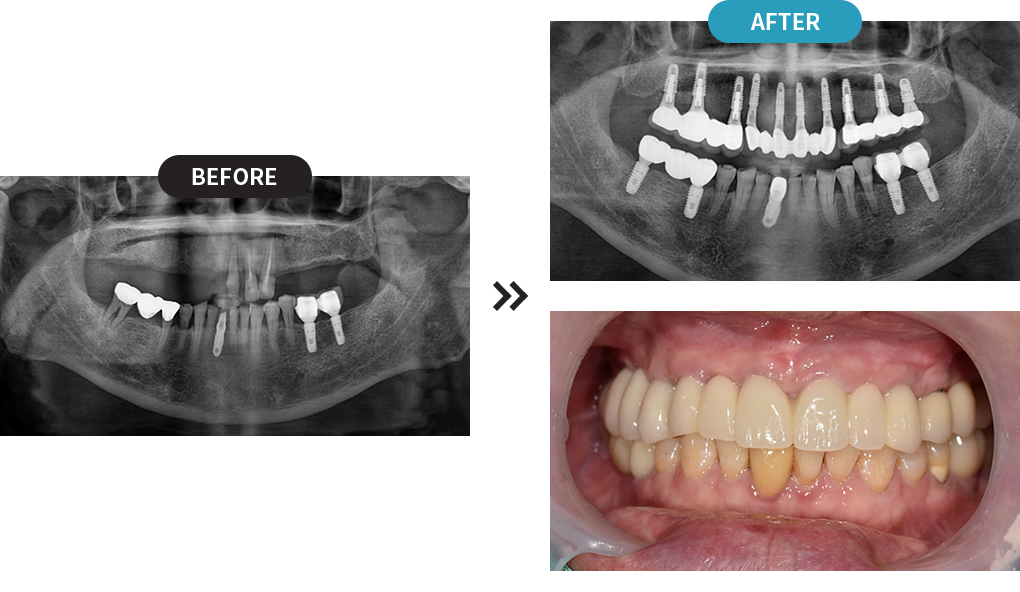

3D디지털 스캔을 활용하여 가장 안전하게 임플란트를

식립할 수 있는 위치를 0.1mm 오차까지 정확하게 계산합니다.

제작된 보철물을 모의 수술을 통해 정해진 임플란트 식립 위치에 빠르고 정확하게 식립합니다.